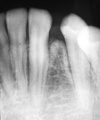

Osteosarcoma

Freq in long bones: proximal tibia/distal femur, in pubescent boys. Gnathic osteosarcs = older age, average 35. X-ray hallmarks of osteosarcoma: asymm widening of PDL space; bone formation in soft tissue; bone formation above the alveolar crest. Spiking root resorption; irregular, ill-defined borders; may be RL to Mixed to RO; “Sun-burst” only in 25% of jaw osteosarcs. Radical resection is only effective tx.